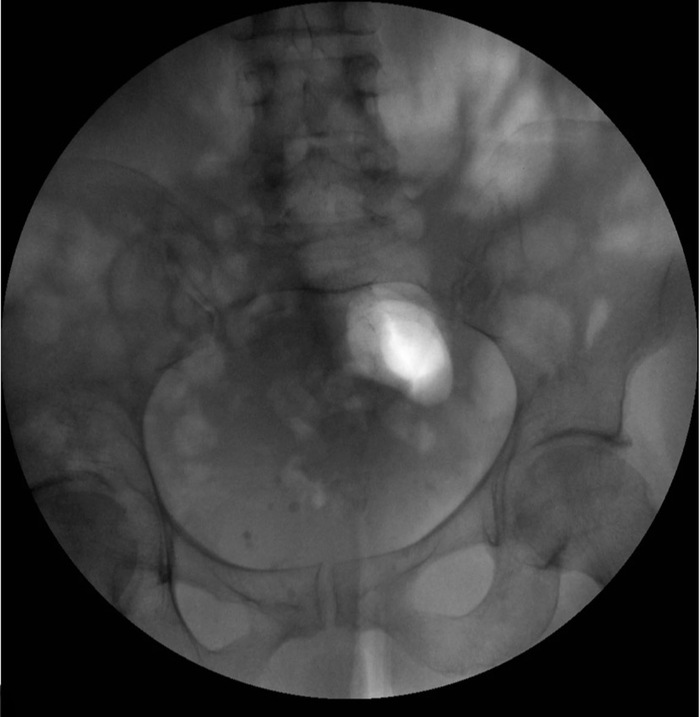

На следующий день, когда с ней снова связались по телефону, пациентка отказалась от госпитализации, заявив, что она самостоятельно смогла извлечь расширитель (вероятнее всего при мочеиспускании, игрушка вклинилась в мочеиспускательный канал, а женщина мануально выдавила его через уретру *комментарий админа Немедицины). УЗИ и рентгенологическое исследование таза подтвердили отсутствие инородного объекта.

Figure 3. Рентген малого таза после извлечения инородного тела